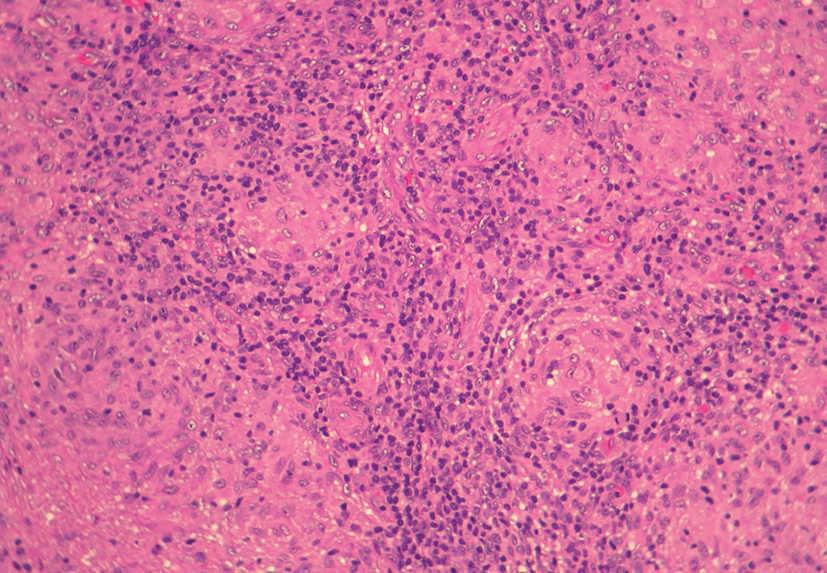

Se realizó una biopsia de la lesión facial y del borde activo de la placa del antebrazo. El estudio histológico mostró, bajo una epidermis respetada, un infiltrado granulomatoso dérmico (fig. 3). Los granulomas eran de tipo tuberculoide, aunque sin necrosis caseosa central. Estos granulomas eran confluentes, formados por histiocitos, algunos de aspecto espumoso y escasas células de Langhans. En la periferia de los granulomas se observaban abundantes linfocitos (fig. 4). En la tinción con de Ziehl-Neelsen no se detectaron bacilos ácido-alcohol resistentes.

Fig. 4.--Detalle de los granulomas tuberculoides formados por histiocitos y con abundantes linfocitos en la periferia. (Hematoxilina-eosina, x20.)